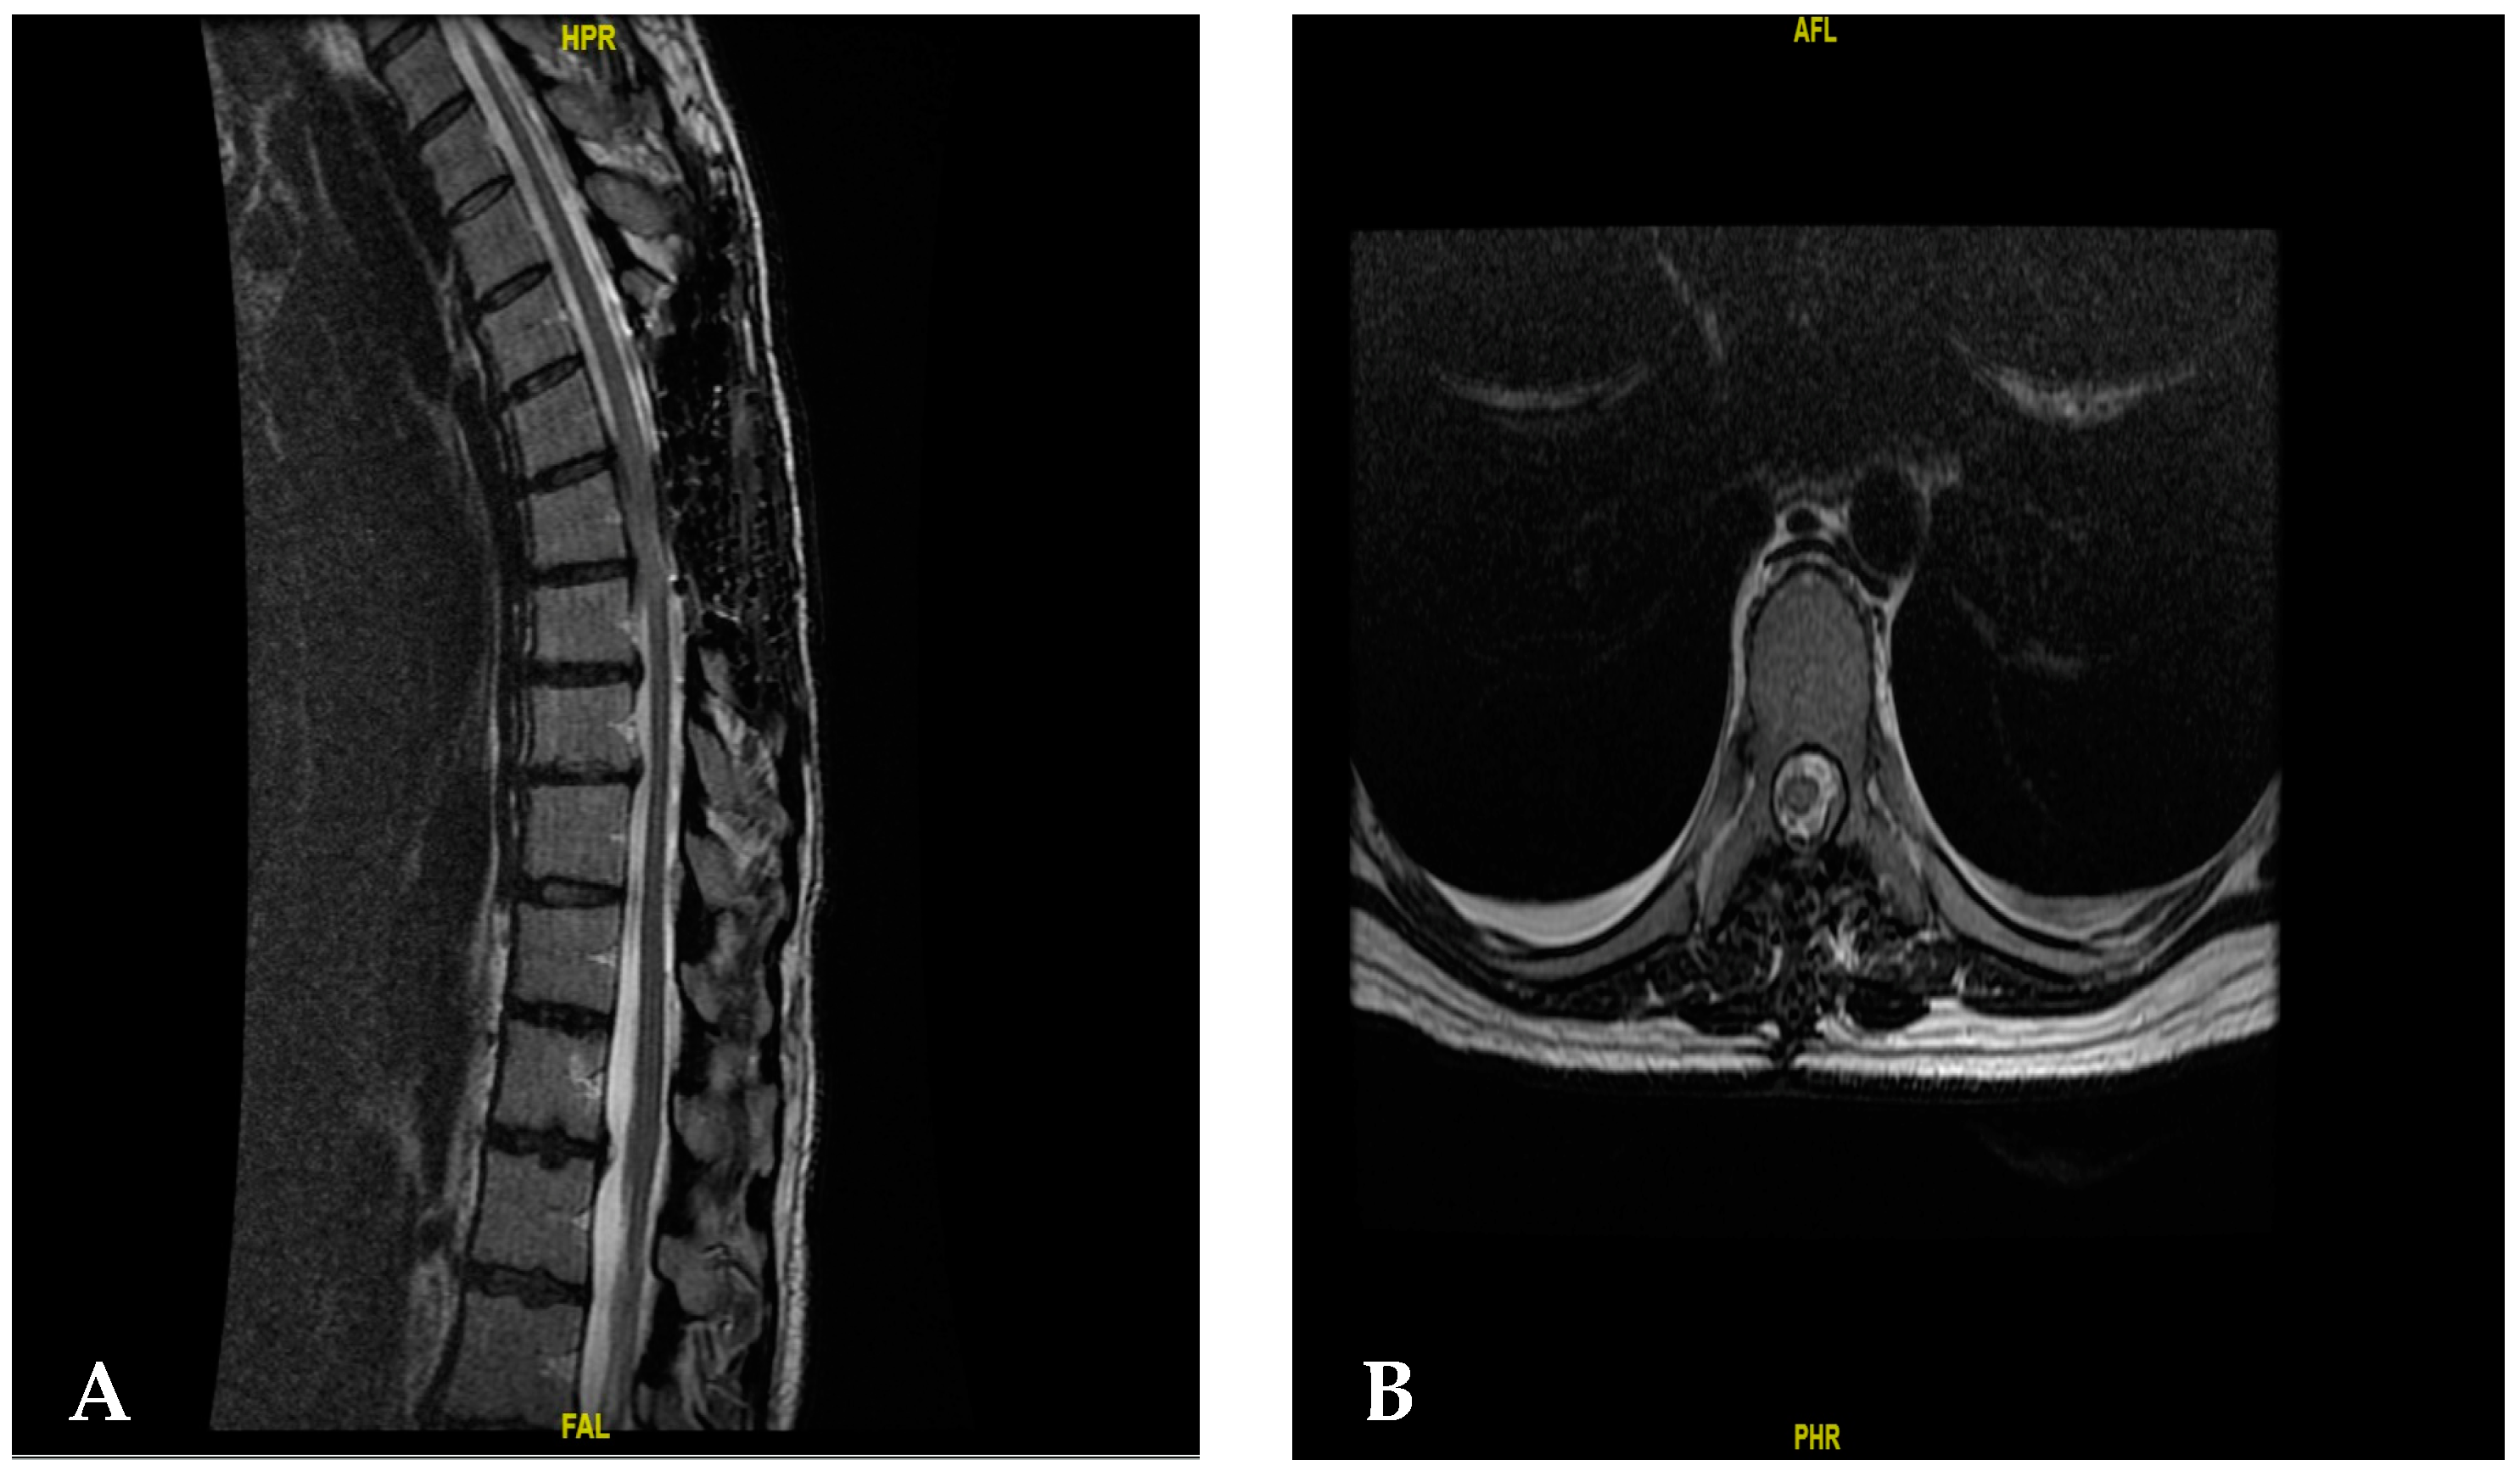

2. Case Presentation